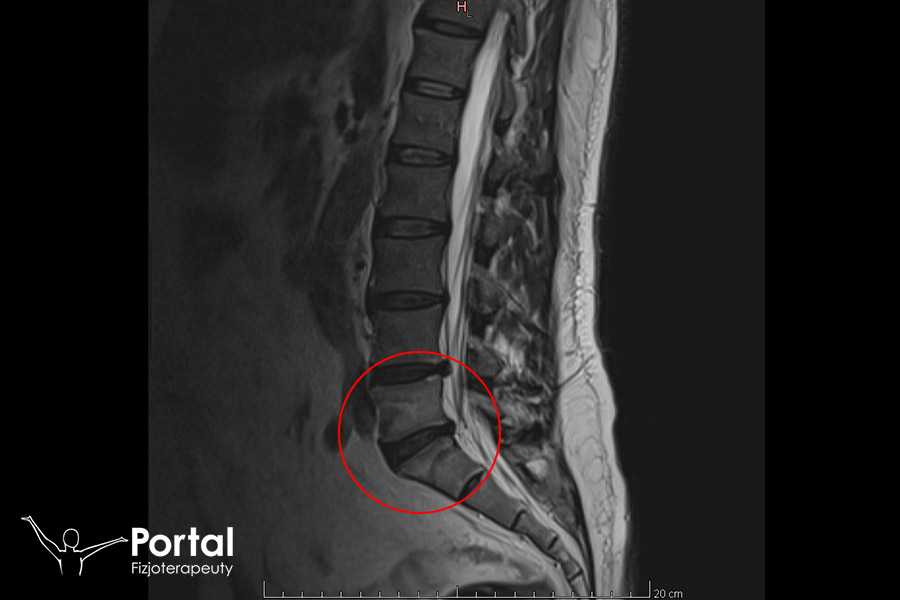

Modic

Modic to typ zmian w kręgosłupie, które są bardzo poważną patologią dotyczącą większości osób zmagających się z przepukliną kręgosłupa. Odnoszą